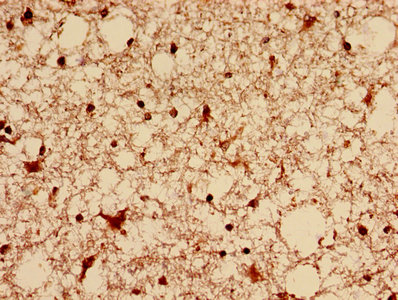

Immunohistochemistry analysis of human brain tissue using CSB-PA007078EA01HU at dilution of 1:100